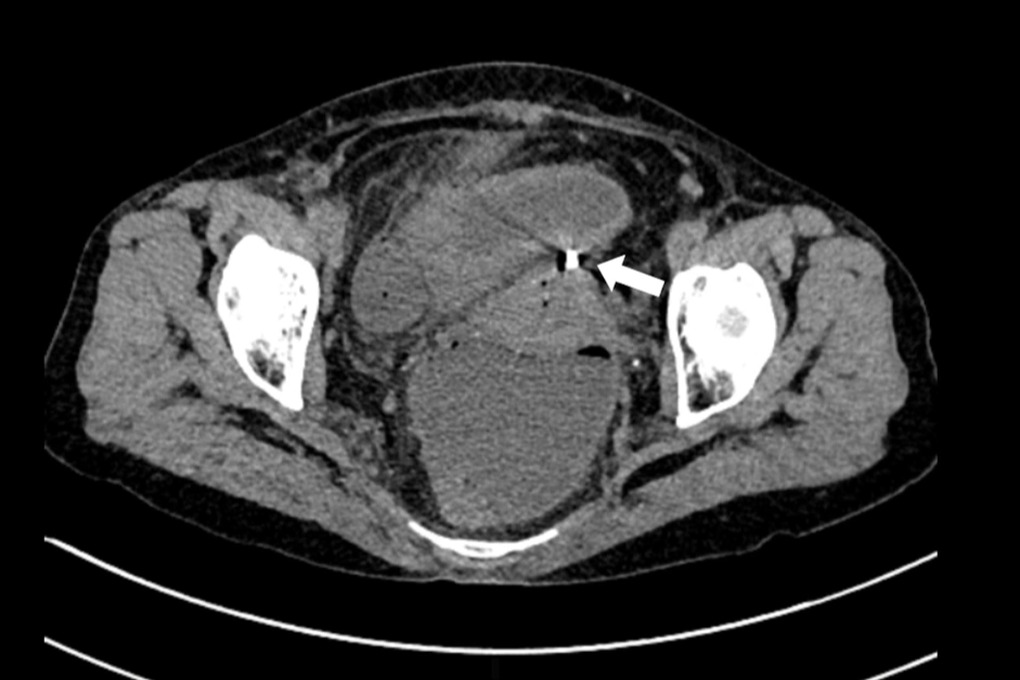

Bà đến Bệnh viện Bạch Mai trong tình trạng bụng có biểu hiện của viêm phúc mạc như bụng chướng, ấn đau. Siêu âm ổ bụng cho thấy các quai ruột ứ đọng dịch, giảm nhu động. Chụp cắt lớp vi tính thấy hình ảnh dịch khí tự do trong ổ bụng, tắc ruột cơ năng, dày thành ruột vị trí hố chậu phải và dị vật xuyên thủng đáy tử cung.

Các triệu chứng lâm sàng có thể gặp do thủng tử cung bao gồm chảy máu bất thường và đau bụng. Vòng tránh thai có thể được nhìn thấy khi làm siêu âm đầu dò âm đạo, nhưng cũng có thể sử dụng chụp cắt lớp vi tính để xác định vị trí.

Đa số vòng tránh thai sau khi thủng sẽ nằm ở khoang phúc mạc sau đó xâm lấn vào các cơ quan lân cận gây biến chứng thủng ruột. Do đặc điểm lỗ thủng ruột thường là nhỏ nên tình trạng viêm phúc mạc có thể ở mức độ nhẹ, khu trú, thậm chí không có triệu chứng.